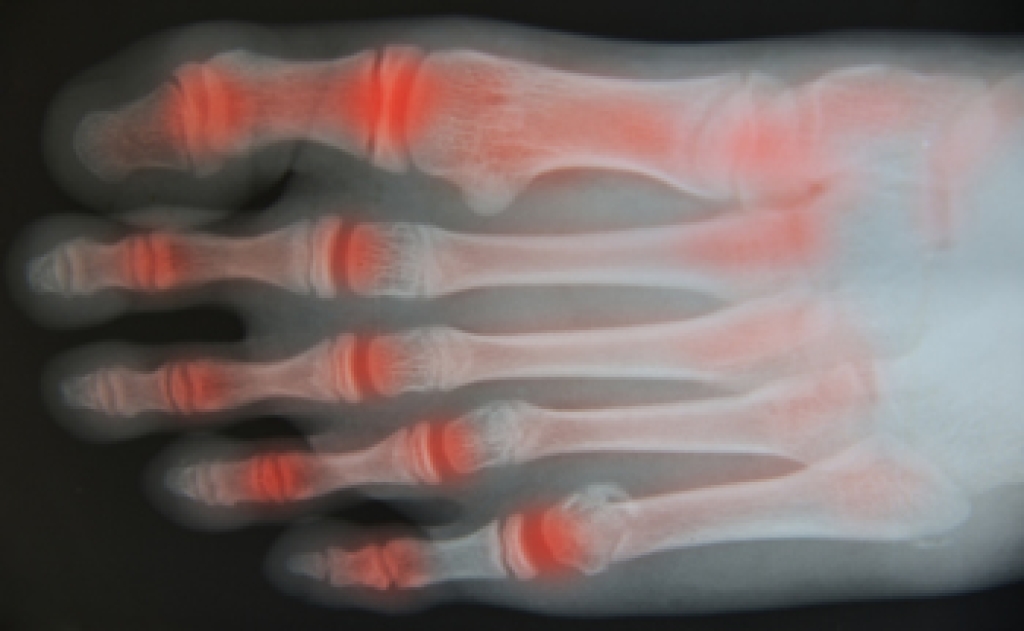

Rheumatoid Arthritis (RA) is an autoimmune disorder in which the body’s own immune system attacks the membranes surrounding the joints. Inflammation of the lining and eventually the destruction of the joint’s cartilage and bone occur, causing severe pain and immobility.

Rheumatoid Arthritis of the Feet

Although RA usually attacks multiple bones and joints throughout the entire body, almost 90 percent of cases result in pain in the foot or ankle area.

- Swelling and pain in the feet

- Stiffness in the feet

- Pain on the ball or sole of feet

- Joint shift and deformation